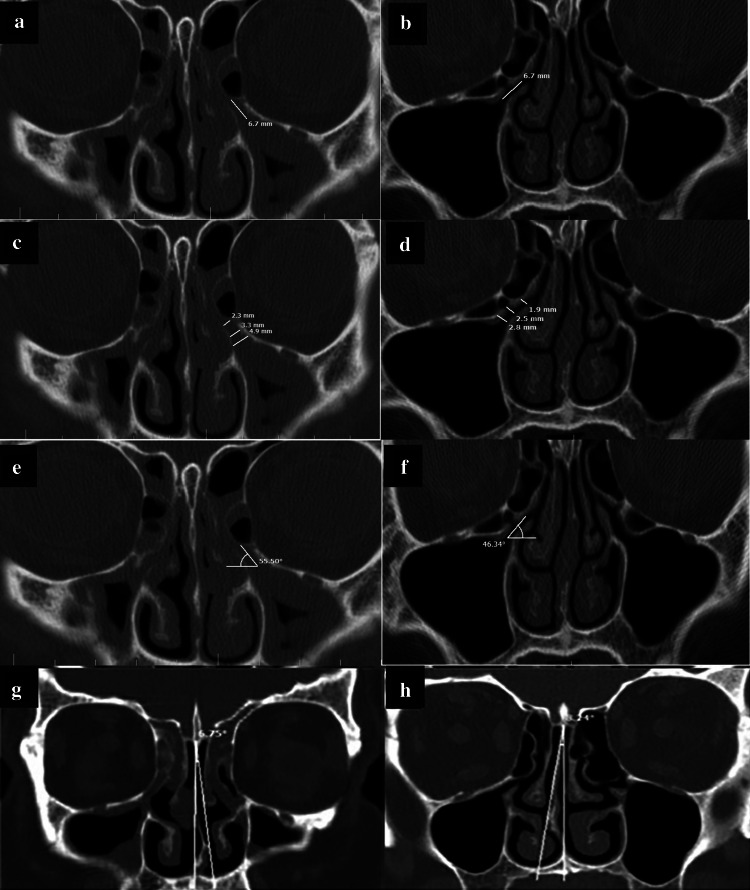

To measure the width, length and angulation of EI and NSD, the ruler and angle features of the PACS software were used on coronal sections (Fig. 2a–h).

Fig. 2.

Measuring the length, width and angle of EI and NSD in the two groups with/without maxillary sinusitis; a, b Measuring the length; c, d Measuring the width; e, f Measuring the angle; g, h Measuring the degree of NSD

Length of EI

To measure the length of EI, the distance between the initiation of ostium and the free end of UP was measured and reported in millimeters (Fig. 2a–b).

Width of EI

To measure the width of EI, three areas were selected along its path (initiation, center, and end), and the distance between the UP and the medial or inferomedial wall of the orbit (or HC if present) was measured in millimeters. The mean of the three values was calculated to determine the final mean width of the EI (Fig. 2c, d).

Angle of EI

The angle between the line passing through the center of EI and the horizontal line (which was parallel to the line tangent to the most inferior point of the maxillary sinus floor) was considered as the angle of EI (Fig. 2e, f).

NSD

The angle formed between the line passing through the crista galli to the anterior nasal spine and the most prominent point of the deviated septum was considered as the angle of NSD (Fig. 2g, h). Also, according to a study by Orlandi et al. [19] who reported 10° septal deviation as the cutoff point, the obtained NSD values were categorized into two groups of NSD < 10°, and NSD ≥ 10°, and the two groups were compared in this respect. Moreover, the form of EI was divided into three types based on the attachment of the UP to lamina papyracea (type A), cribriform plate (base of skull) (type B), and middle concha (type C) as shown in Fig. 3. All CT scans were evaluated by a senior post-graduate student of oral and maxillofacial radiology under the supervision of an oral and maxillofacial radiologist.